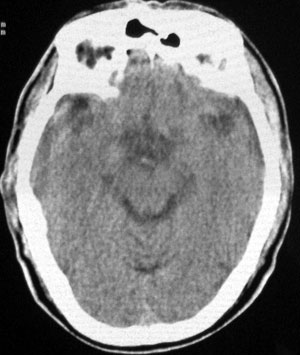

男性,65岁,头疼。 看看这大脑镰,ct值约83hu .

大脑镰密度高只是一个方面,如果两侧蛛网膜下腔密度及宽度无改变,则无异常。临床可除外蛛血。

男性,65岁,头疼。 看看这大脑镰,ct值约83hu .考虑蛛血,应该结合临床